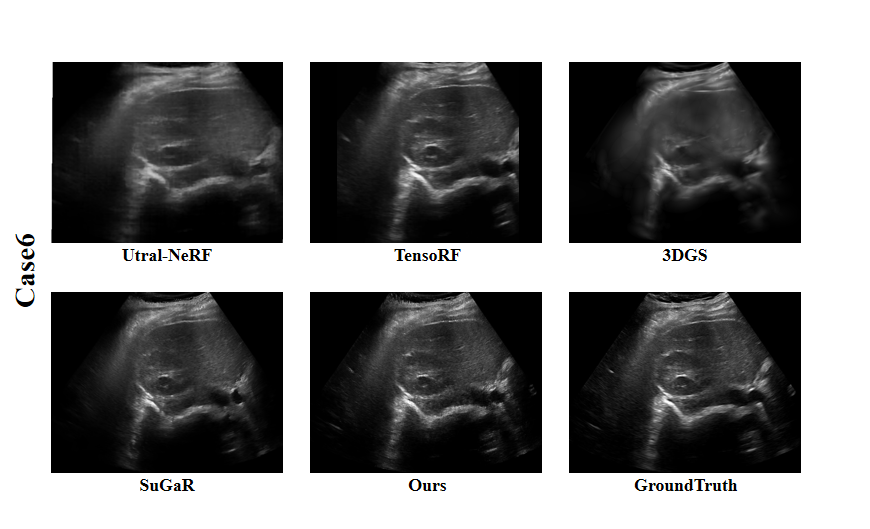

Refer to caption

Figure 9: Visual Comparison fo Case 6 in the Clinical Dataset.

From the supplementary experimental results of Fig.6-9 on the Clinical Dataset, UltraGS showed significant advantages in multiple typical cases (Case 1 to Case 6). Compared with other methods [mildenhall2021nerf, chen2022tensorf, wysocki2024ultra, kerbl20233d, guedon2024sugar], UltraGS has achieved better results in the restoration of boundary details, preservation of tissue structure, and clarity of overall reconstruction, demonstrating its robustness and generalization ability in processing complex clinical data. These results fully validate the adaptability of our method in real clinical environments, especially in the face of poor image quality or blurry structural features, UltraGS can still accurately capture key structural information and achieve stable and high-quality novel view synthesis.